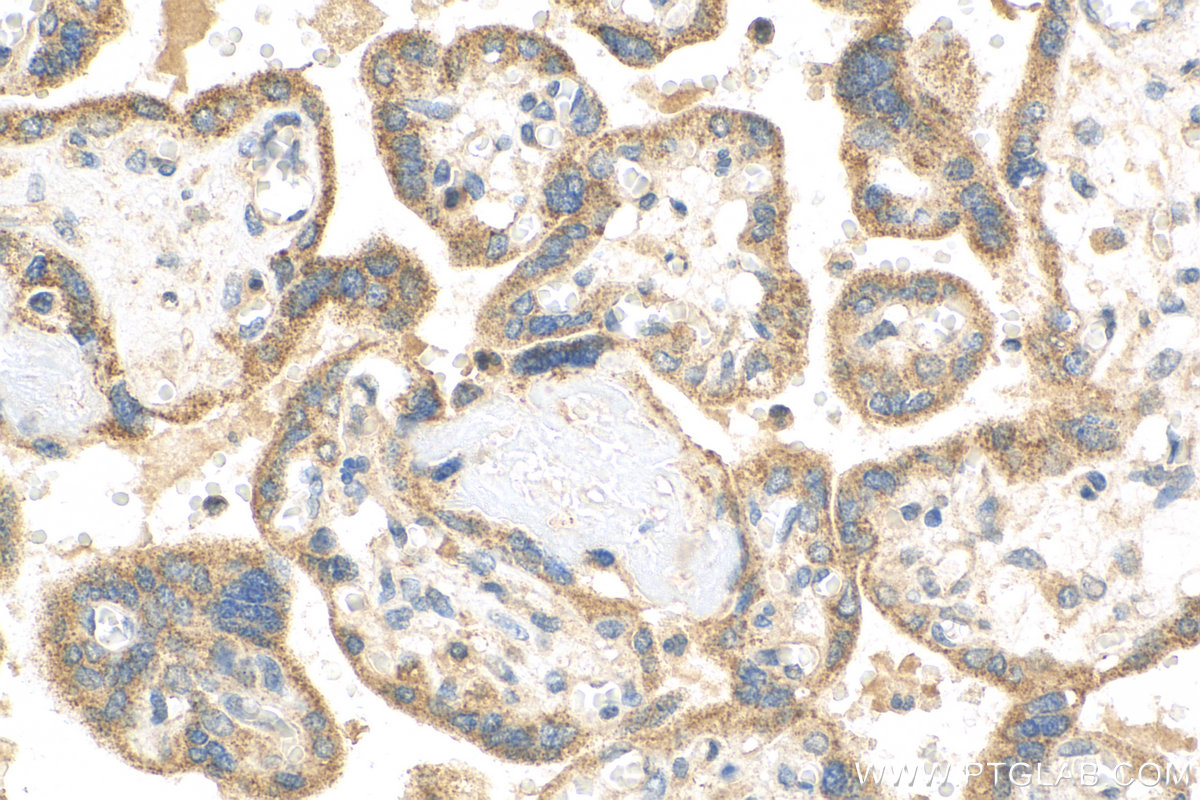

| Positive IHC detected in | human placenta tissue, human lung tissue, mouse lung tissue Note: suggested antigen retrieval with TE buffer pH 9.0; (*) Alternatively, antigen retrieval may be performed with citrate buffer pH 6.0 |

| Immunohistochemistry (IHC) | IHC : 1:50-1:500 |